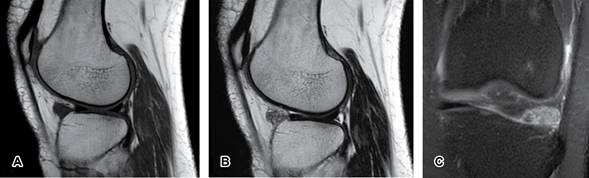

Mujer de 55 años de edad, refiere caída de su propia altura sobre rodilla izquierda presentando dolor moderado en la región anterolateral y limitación funcional, como único antecedente: múltiples microtraumatismos previos en rodilla. Se le solicita resonancia magnética simple (Figura 1) identificando imagen característica de condromatosis sinovial, después se realiza artroscopia con resección de fragmentos condrales libres (Figura 2), sin observar cambios en tejido sinovial y se envían a patología, confirmando la alteración (Figura 3).

Figura 1: Resonancia magnética de rodilla izquierda. A) Sagital T1. B) Sagital T2. C) Coronal en DP FS. Imagen nodular intraarticular anterior al cuerno anterior del menisco lateral, de comportamiento isointenso en T1, heterogéneo con señal intermedia-alta en T2 e hiperintenso en DPFS, con ausencia de efecto de masa.